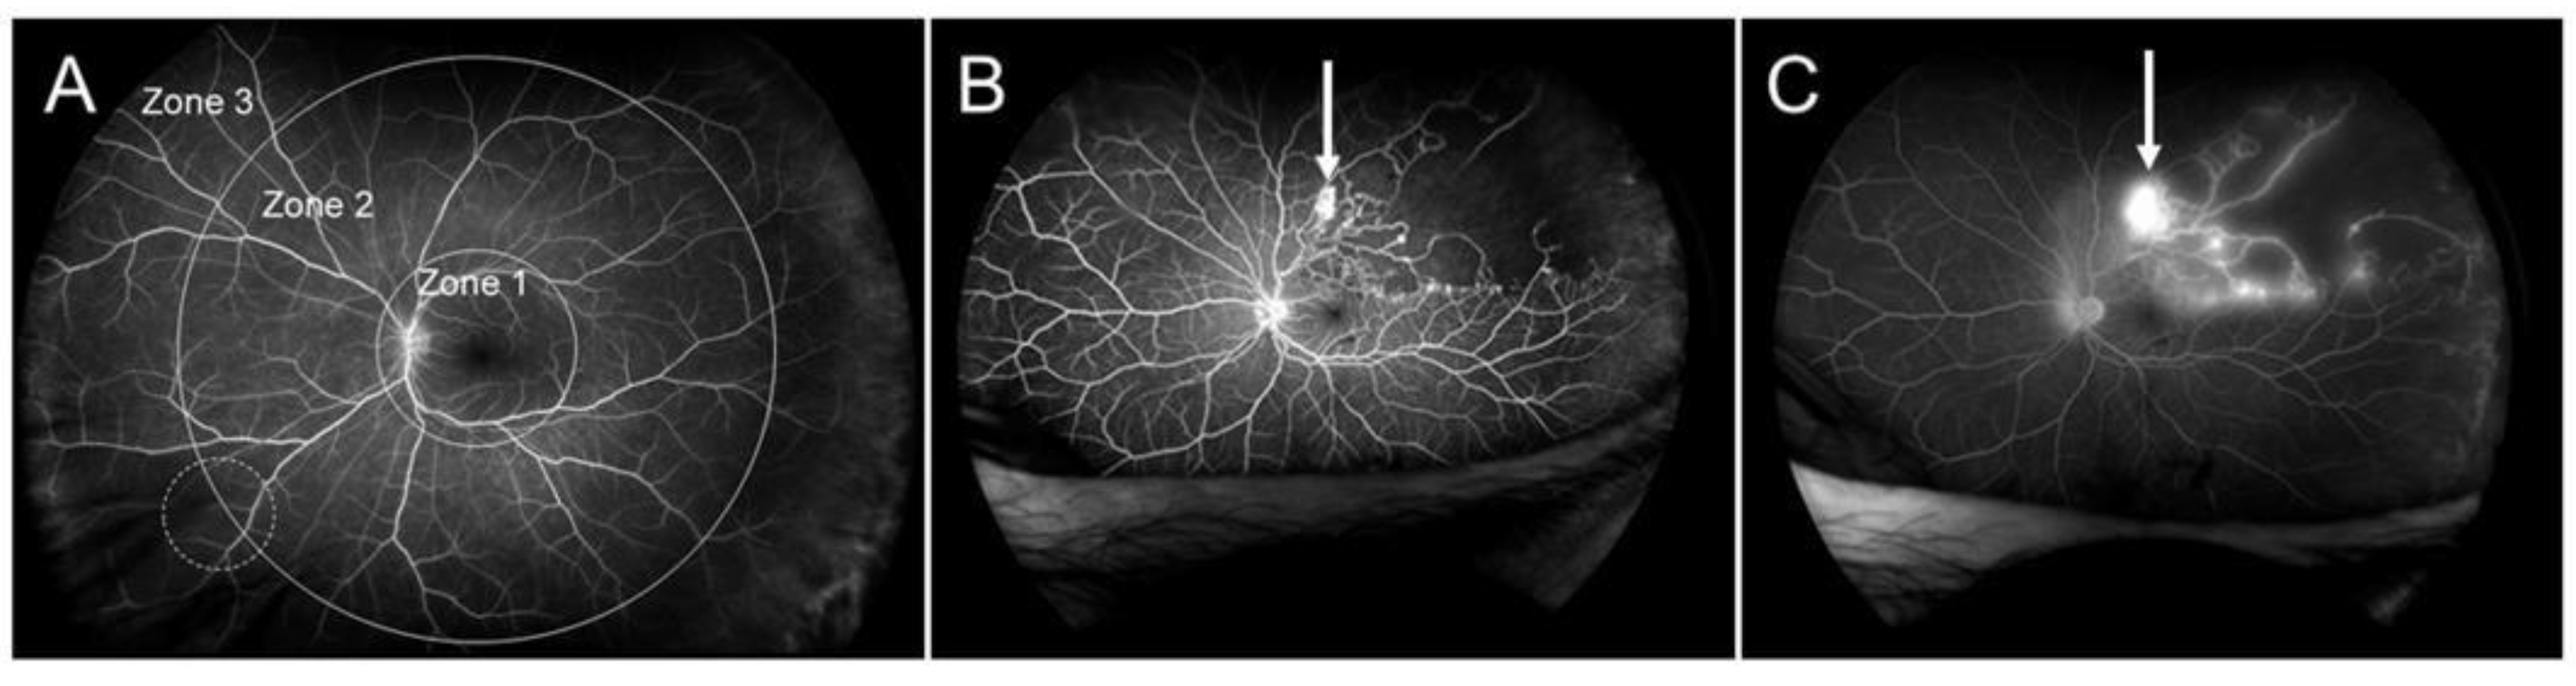

3.9. Neovascularization

- Yasuda, Y.; Hirano, Y.; Esaki, Y.; Tomiyasu, T.; Suzuki, N.; Yasukawa, T.; Yoshida, M.; Ogura, Y. Peripheral microvascular abnormalities detected by wide-field fluorescein angiography in eyes with branch retinal vein occlusion. Ophthalmic Res. 2019, 61, 107–114. [Google Scholar] [CrossRef] [PubMed]

- Huemer, J.; Khalid, H.; Wagner, S.K.; Nicholson, L.; Fu, D.J.; Sim, D.A.; Patel, P.J.; Balaskas, K.; Rajendram, R.; Keane, P.A. Phenotyping of retinal neovascularization in ischemic retinal vein occlusion using wide field OCT angiography. Eye. Epub. 2020. [Google Scholar] [CrossRef]